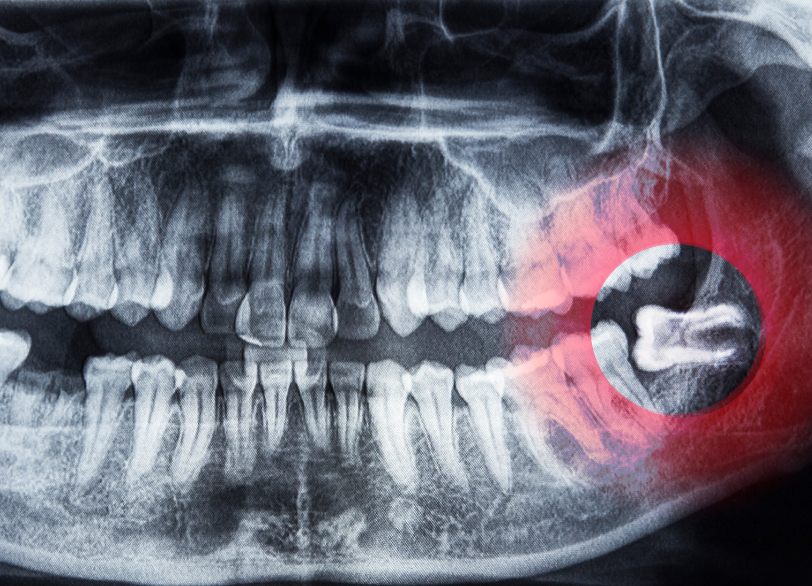

親知らずは永久歯の中で最も奥に、一番後に生えてくる歯です。< 一般的に10代後半から20代前半頃に生え始めますが、現代人は顎が小さくなる傾向にあるため親知らずが正常に生えるための十分なスペースがないケースが増えています。 そのため、横や斜めに傾いて生えたり骨の中に埋まったままだったりと、正常な位置に生えてこないことが多く様々なトラブルの原因となります。

まず、レントゲン撮影を行い親知らずの生え方、歯の根の形、骨の中に埋まっている深さ、神経や血管との位置関係などを正確に把握します。